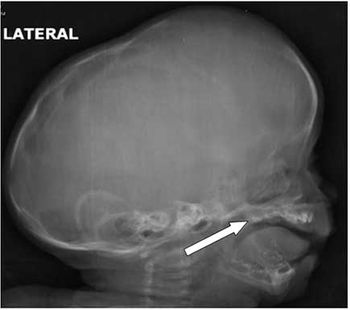

Case History: 3-month-old child with abnormal growth of head size.